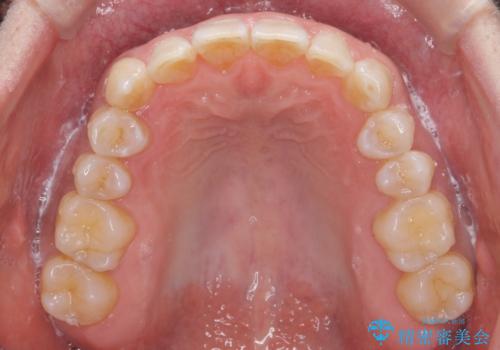

八重歯と下の歯のがたつき マウスピースで

- 右上の犬歯が目立つのが気になる、下の歯並びも治したいとのことで来院。

歯を抜かずに少し削って小さくして並べました。

並びも良くなり、患者様にも喜んでいただきました。

右上の犬歯の歯肉退縮自体は進行する可能性をお伝えしておりましたが、特に変化なく治療できました。